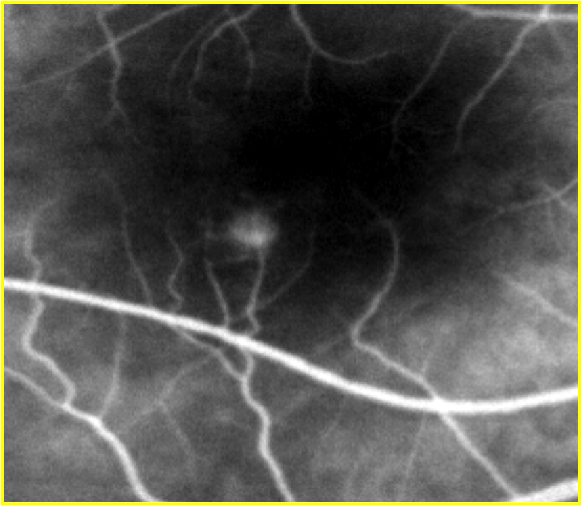

Classification and Interpretation of Fluorescein Angiography

A method of performing and interpreting the retinal vasculature and macular findings so that a specific diagnosis and treatment could be entertained. It led to the development of a book entitled, “Interpretation of Fundus Fluorescein Angiography” by Louis C. Mosby, several years later.

Schatz H, Burton T, Yannuzzi LA, Rabb M: Interpretation of Fundus Fluorescein Angiography: A Comprehensive Text and Atlas. St. Louis, C. Mosby Co., 1978, 750 pages.